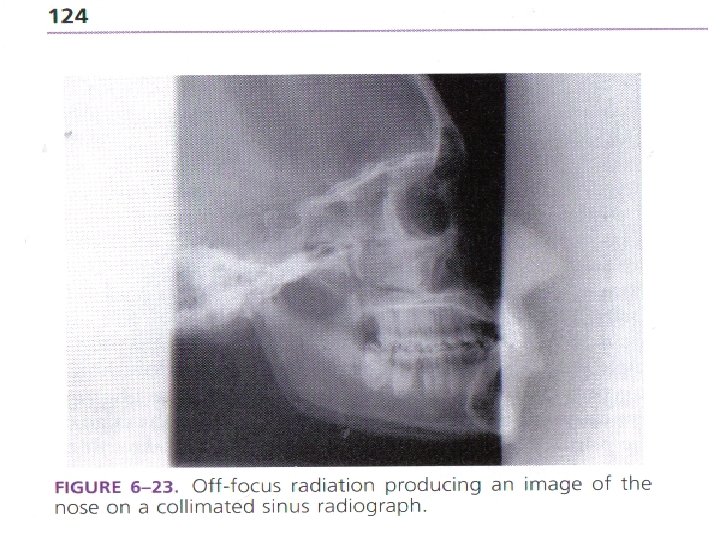

OFF-FOCUS RADIATION Extra focal �Photons �Causes �May not produced at focal spot “ghosting” contribute

OFF-FOCUS RADIATION Extra focal �Photons �Causes �May not produced at focal spot “ghosting” contribute 25 -30% of primary beam